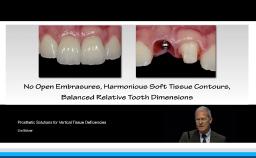

This lecture addresses role of digital imaging in restorative dentistry and discusses its use in facial, dentolabial, phonetic, and dental analysis. This presentation demonstrates the use of imported digital images, an iPad, and the free application iDraw for step-by-step facial analysis of a patient. The lecturer then demonstrates, the design of the smile line, first on the computer and then clinically. Transformation of 2D digital images to 3D images using the DSD Connect software is described. The lecture concludes with a clinical case carried out digitally from start to finish using intraoral scans and CBCT for implant planning and guided surgery.

describe facial, dentolabial, phonetic, and dental analysis